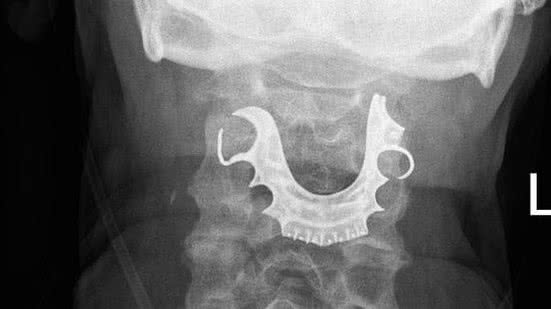

Quando o homem voltou novamente, dois dias depois, a equipe médica examinou mais detalhadamente e encontrou um objeto semi-circular sobre as cordas vocais.

Ele então disse aos médicos que havia perdido sua dentadura - três dentes falsos e uma placa dentária - durante o tempo em que ficou no hospital para a cirurgia.